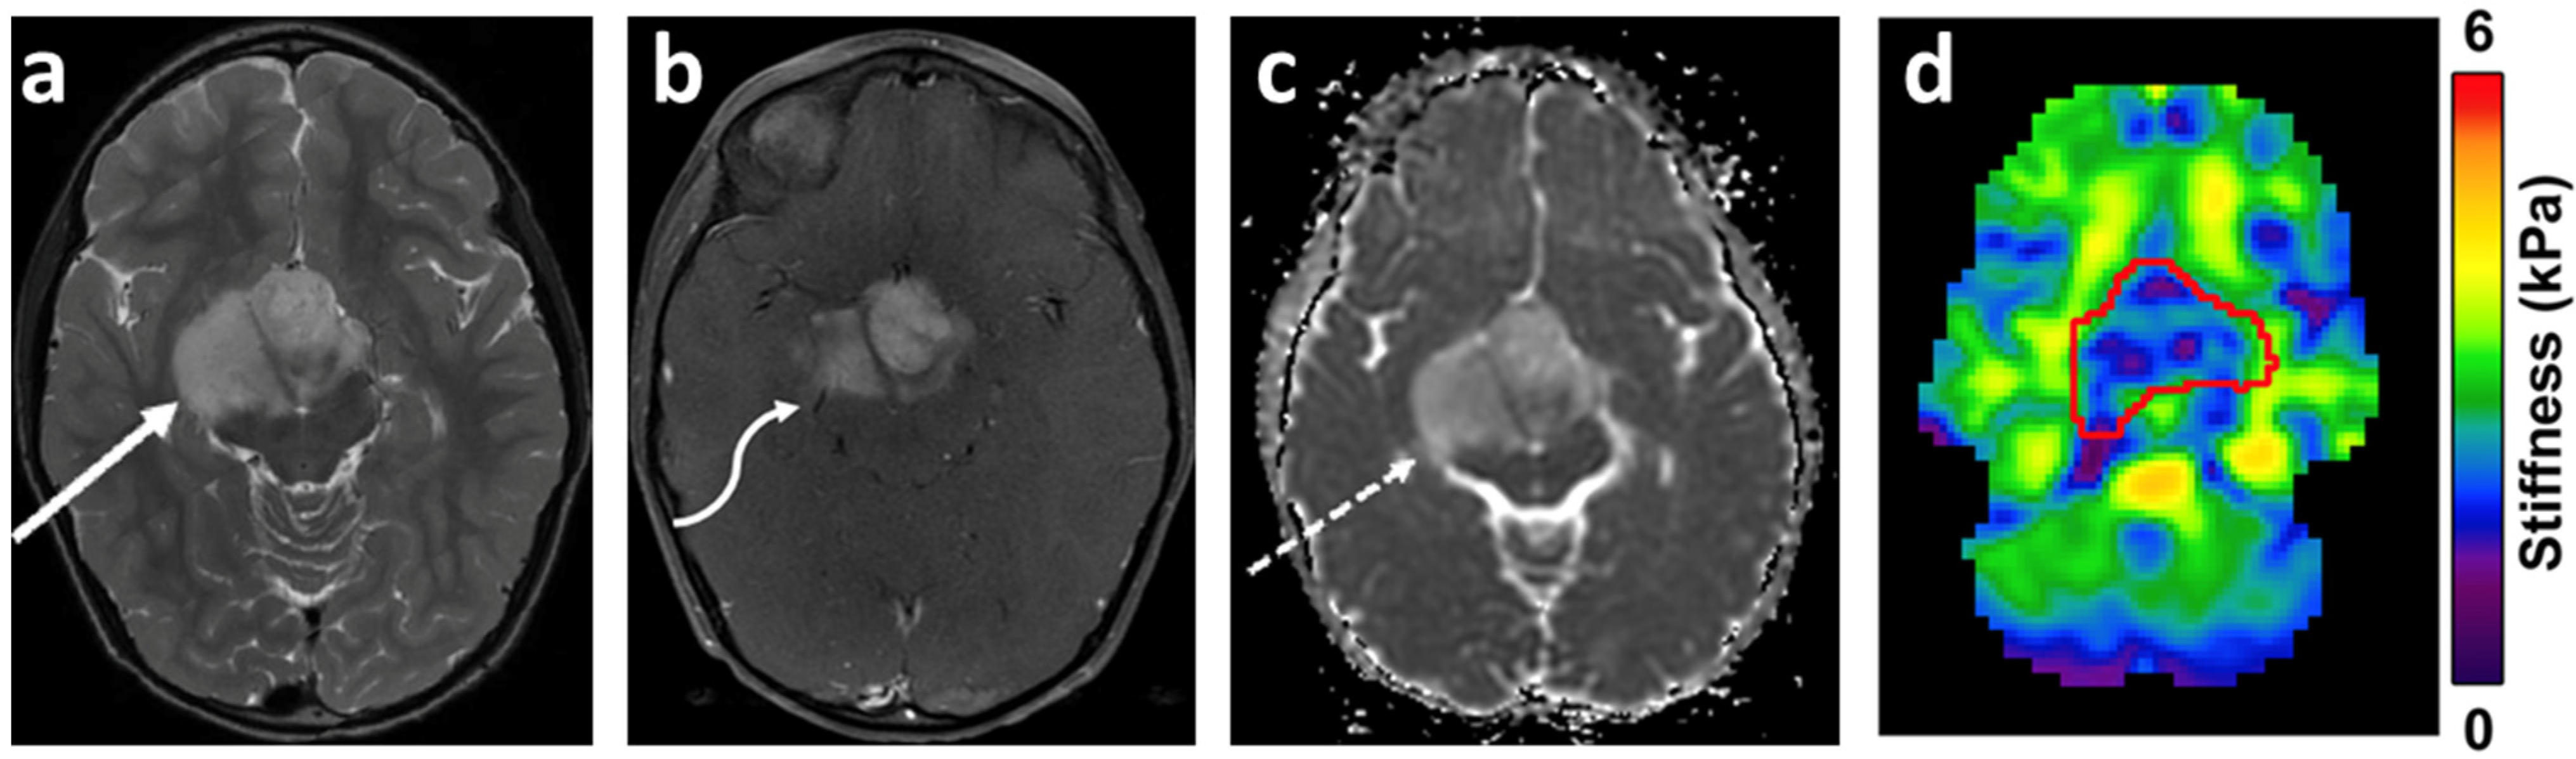

- Manduca, A.; Bayly, P.J.; Ehman, R.L.; Kolipaka, A.; Royston, T.J.; Sack, I.; Sinkus, R.; Van Beers, B.E. MR elastography: Principles, guidelines, and terminology. Magn. Reson. Med. 2020, 85, 2377–2390. [Google Scholar] [CrossRef] [PubMed]

- Bunevicius, A.; Schregel, K.; Sinkus, R.; Golby, A.; Patz, S. REVIEW: MR elastography of brain tumors. NeuroImage Clin. 2019, 25, 102109. [Google Scholar] [CrossRef]

- Reiss-Zimmermann, M.; Streitberger, K.-J.; Sack, I.; Braun, J.; Arlt, F.; Fritzsch, D.; Hoffmann, K.-T. High Resolution Imaging of Viscoelastic Properties of Intracranial Tumours by Multi-Frequency Magnetic Resonance Elastography. Clin. Neuroradiol. 2014, 25, 371–378. [Google Scholar] [CrossRef]

- Streitberger, K.-J.; Reiss-Zimmermann, M.; Freimann, F.B.; Bayerl, S.; Guo, J.; Arlt, F.; Wuerfel, J.; Braun, J.; Hoffmann, K.-T.; Sack, I. High-Resolution Mechanical Imaging of Glioblastoma by Multifrequency Magnetic Resonance Elastography. PLoS ONE 2014, 9, e110588. [Google Scholar] [CrossRef]

- Pepin, K.; McGee, K.; Arani, A.; Lake, D.; Glaser, K.; Manduca, A.; Parney, I.; Ehman, R.; Huston, J. MR Elastography Analysis of Glioma Stiffness andIDH1-Mutation Status. Am. J. Neuroradiol. 2017, 39, 31–36. [Google Scholar] [CrossRef]